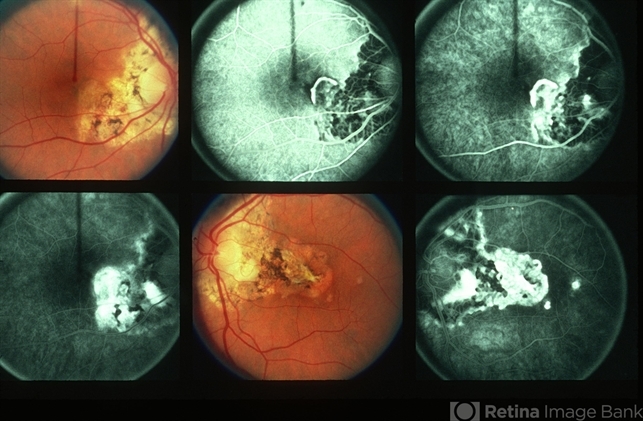

By Howard Schatz, MD

- Uploaded on May 13, 2013.

- Condition/keywords

- geographic helicoid peripapillary choroidopathy (GHPC), subretinal neovascularization (SRNV)

- 53-year-old white female, GHPC, SRNV, histo; 20/40; 8/200.